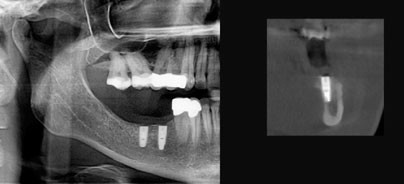

4. Implantologie: Virtuelle Planung von implantatprothetischen Versorgungen, Verknüpfung der 3-D-Daten mit der Konstruktionssoftware von CAD/CAM-Systemen (z.B. für CAD/CAM-gefertigte Bohrschablonen). Aber auch bei sogenannten Standardindikationen liefert die dreidimensionale Darstellung wertvolle Informationen zur Positionierung der Implantate, die durch eine summarische zweidimensionale Darstellung nicht verfügbar sind (Abb. 1). Die dreidimensionale präimplantologische Diagnostik ist daher zu einem unverzichtbaren Planungshilfsmittel in vielen Indikationen der Implantatprothetik geworden.